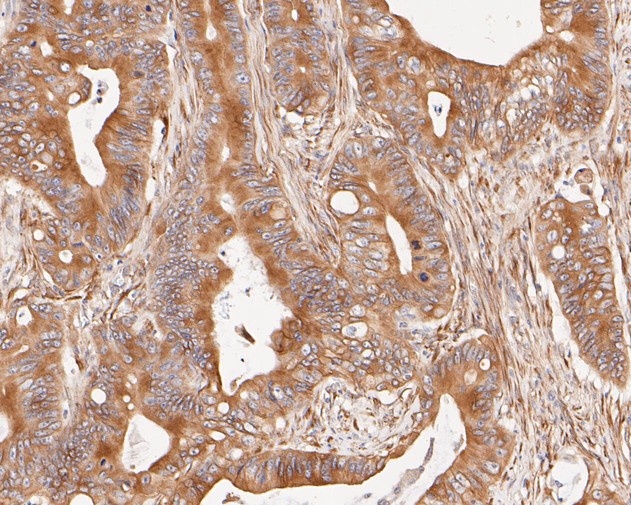

Immunohistochemical analysis of paraffin-embedded human colon carcinoma tissue using anti-Cytokeratin 20 antibody. The section was pre-treated using heat mediated antigen retrieval with Tris-EDTA buffer (pH 8.0-8.4) for 20 minutes.The tissues were blocked in 5% BSA for 30 minutes at room temperature, washed with ddH2O and PBS, and then probed with the primary antibody (EM1901-96, 1/500) for 30 minutes at room temperature. The detection was performed using an HRP conjugated compact polymer system. DAB was used as the chromogen. Tissues were counterstained with hematoxylin and mounted with DPX.